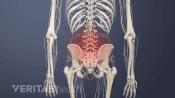

Injections relieve neck and back pain by delivering medications directly to the affected area, reducing inflammation.